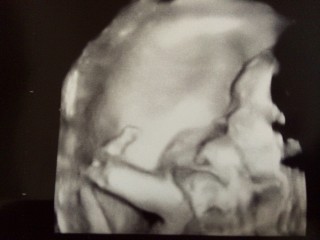

妊娠したときからなんとなく男の子かなぁ?と思っていたところ、今回の検診で男の子と判明*°初産婦にしては早く17週から胎動を感じていて、もうお腹の外からうごきがわかるほどです!よっぽど元気な男の子なんだろうなぁ☆エコーは横顔、お父さんに口元がそっくりで笑っちゃいました(*^^*)こうやって顔が見えると、食べ物、水、サプリメント…これまで以上に質のいい栄養をとってあげなきゃとやる気がでます。妊娠前からべんきと身体作りをしてきたことが大きな自信になっています。週数より大きめなのは栄養のおかげかな?♪お母さんはがんばるよー!すくすく大きくなってね!